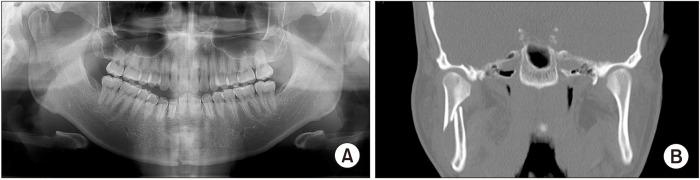

A transparotid approach, with a retromandibular or preauricular incision, is an alternative surgical approach for treating a subcondylar fracture and reducing the potential for complications such as injury to the facial nerves. However, retromandibular and preauricular incisions are both created far away from the parotid gland-dissection area. Thus, it is necessary to undermine the skin and retract it anteriorly to access the surgical field. Here, we introduce a modified approach wherein the incision allows for direct access to the fracture site. This approach may be adopted to shorten the incision length, reduce the retraction trauma at the surgical site, and help prevent injury to the facial nerve.

采用下颌后或耳前切口的透明入路是治疗髁突骨折和降低诸如面神经损伤等并发症可能性的另一种手术方法。然而,下颌后和耳前切口均远离腮腺解剖区域。因此,有必要分离皮肤并向前牵拉以进入手术视野。在此,我们介绍一种改良方法,该方法通过切口可直接进入骨折部位。可采用此方法缩短切口长度,减少手术部位的牵拉创伤,并有助于防止面神经损伤。